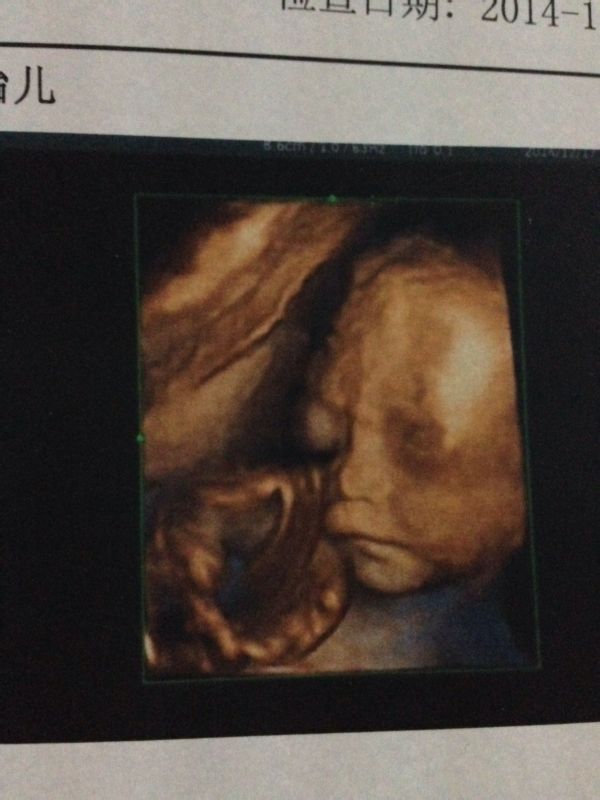

我怀孕24周去做三维彩超照宝宝的照片显得上嘴唇很大,问医生说没问题,请问他出生嘴巴也是那么大吗? 点击展开 匿名用户 2015-02-19 18:30 为您推荐: 其他回答 你好,彩超可观察宫内胎儿的生长发育情况,能排查唇裂,脊柱裂,大脑、肾、心脏、骨骼发育等。是排畸的最好方法。彩超只是初步判断有没有畸形对宝宝的面容出生后是否漂亮不能确定的。 超级宝宝守护神 2015-02-19 21:20 相关问题 怀孕中期错过了唐筛检查时间,只做了三维彩超,医生说胎儿健康,因为舟山这边还没有做四维的,听别人 宝宝今天摔倒了嘴里流了好多血、洗了后上嘴唇有牙齿印嘴巴肿了怎么办 宝宝嘴巴上有两个白白泡泡一样,下嘴唇还有几道红印子,怎么办啊